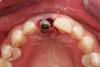

Due to the young man's college schedule and consequent time constraints, he was appointed the next day. A surgical guide was not used because there was limited time and there was an appropriate amount of thick soft-tissue profile, measured amount of bone volume based on the CBCT, and virtual placement of the dental implant. Figure 7 and Figure 8 showed the measurements to be more than 2 mm buccal and lingual to the proposed implant placement. The interproximal dimensions mesial and distal to the implant proposal were greater than the 1.5 mm previously mentioned in this article. The CBCT images provided the spatial dimensions and a mental awareness regarding implant placement angulation. The final position was predetermined and acceptable for the considerations necessary in choosing the abutment (zirconia or titanium) and final restoration. Because the implant had appropriate bone length and abundant 360-degree bone volume, minimal augmentation was needed. The natural clinical crown was used to provide an ideal emergence profile to enhance the soft-tissue architecture. Atraumatic tooth extraction was extremely helpful in the development of this treatment plan. Having 1.5 mm to 2 mm of facial bone available after the extraction would facilitate exceptional healing and long-term results. Figure 9, occlusal view, depicted a thick soft-tissue profile and properly placed implant within the arch form.

Fig 9. Occlusal view, implant placement after extraction, buccal plate intact.

Figure 9